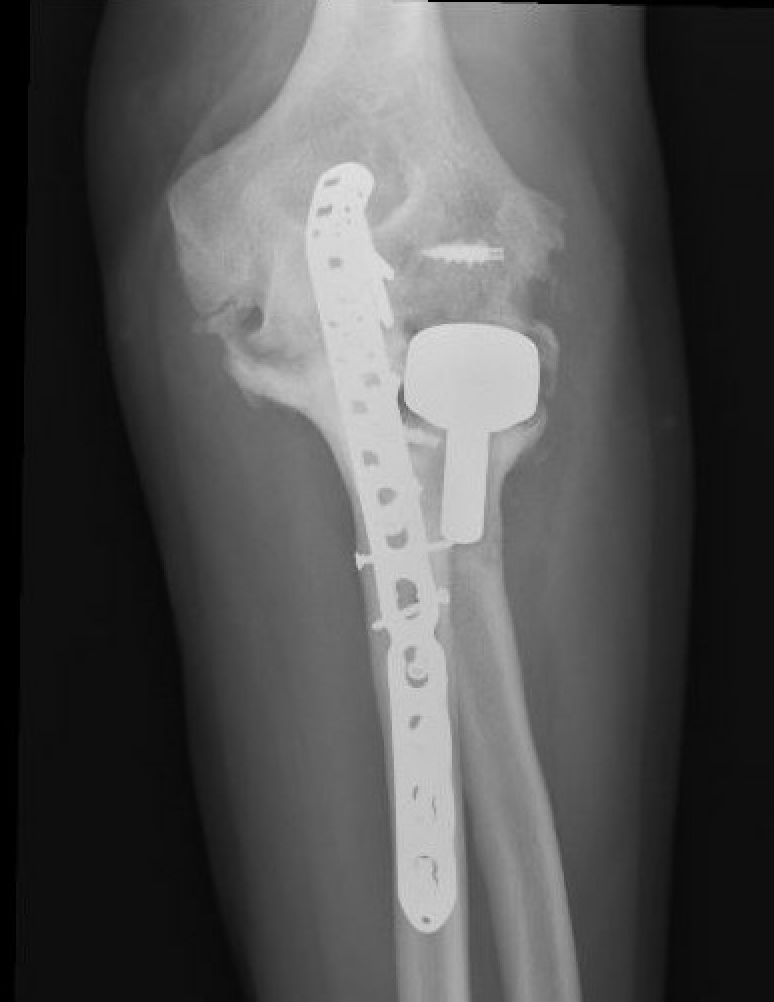

Olecranon plate + ORIF Type II coronoid process + radial head replacement

Olecranon plate with radial head replacement

Olecranon plate with radial head replacement + LCL repair

Olecranon plate + medial coronoid buttress plate + radial head replacement